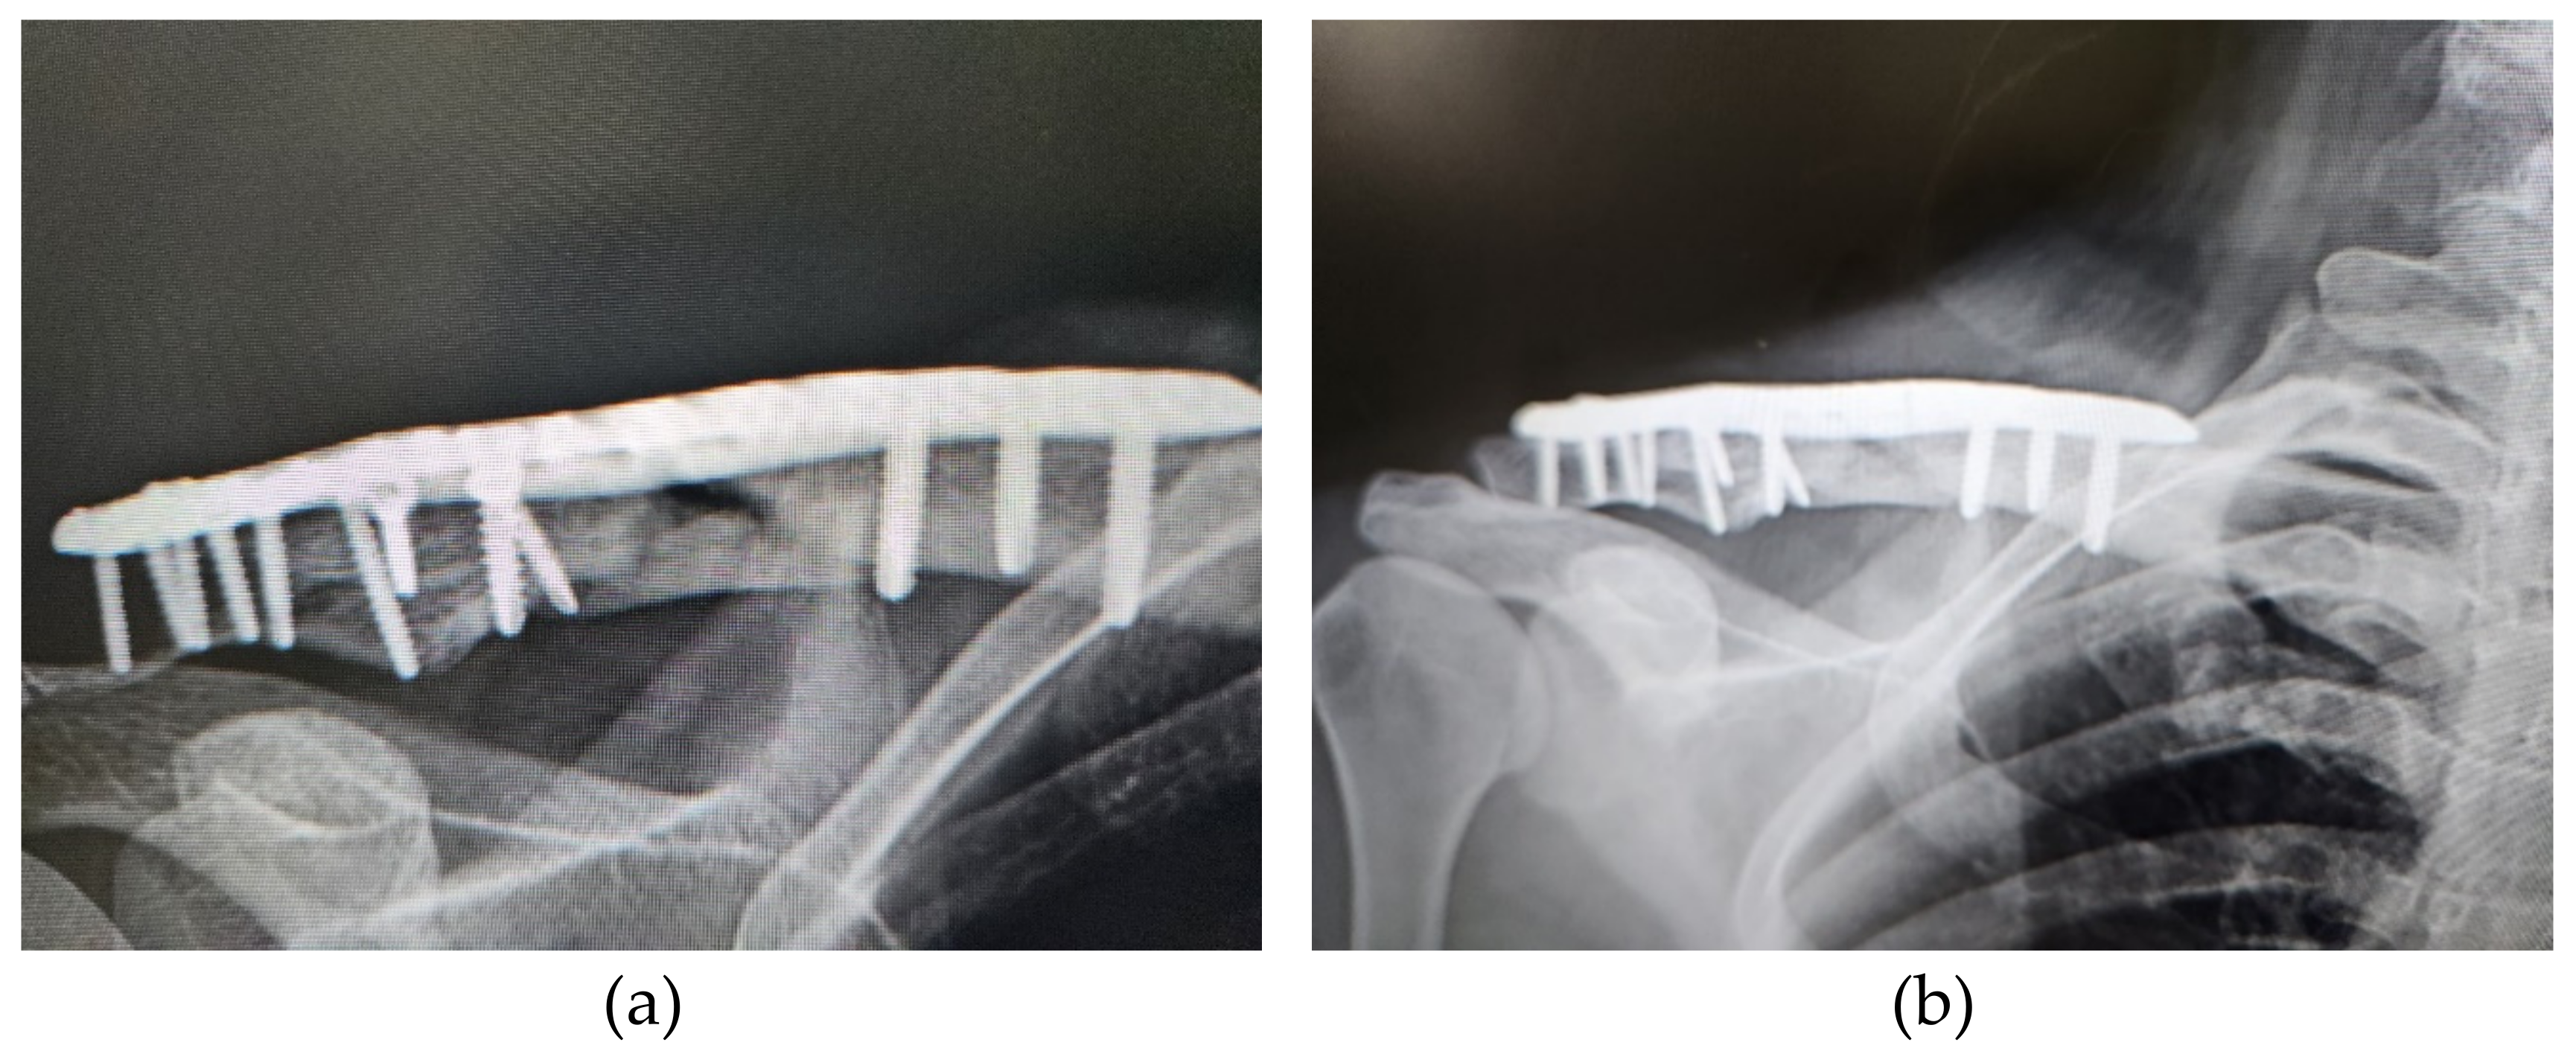

| 4 | 39 | Female | Right clavicle fracture | Non-union after ORIF | 9 | 2 | Union |